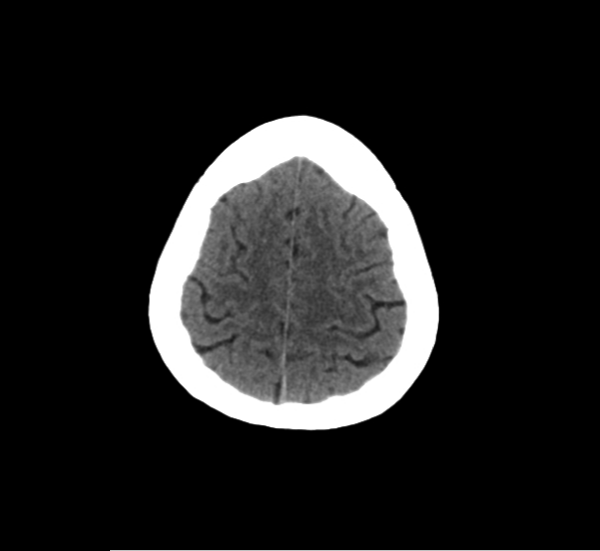

CT Brain Anatomy